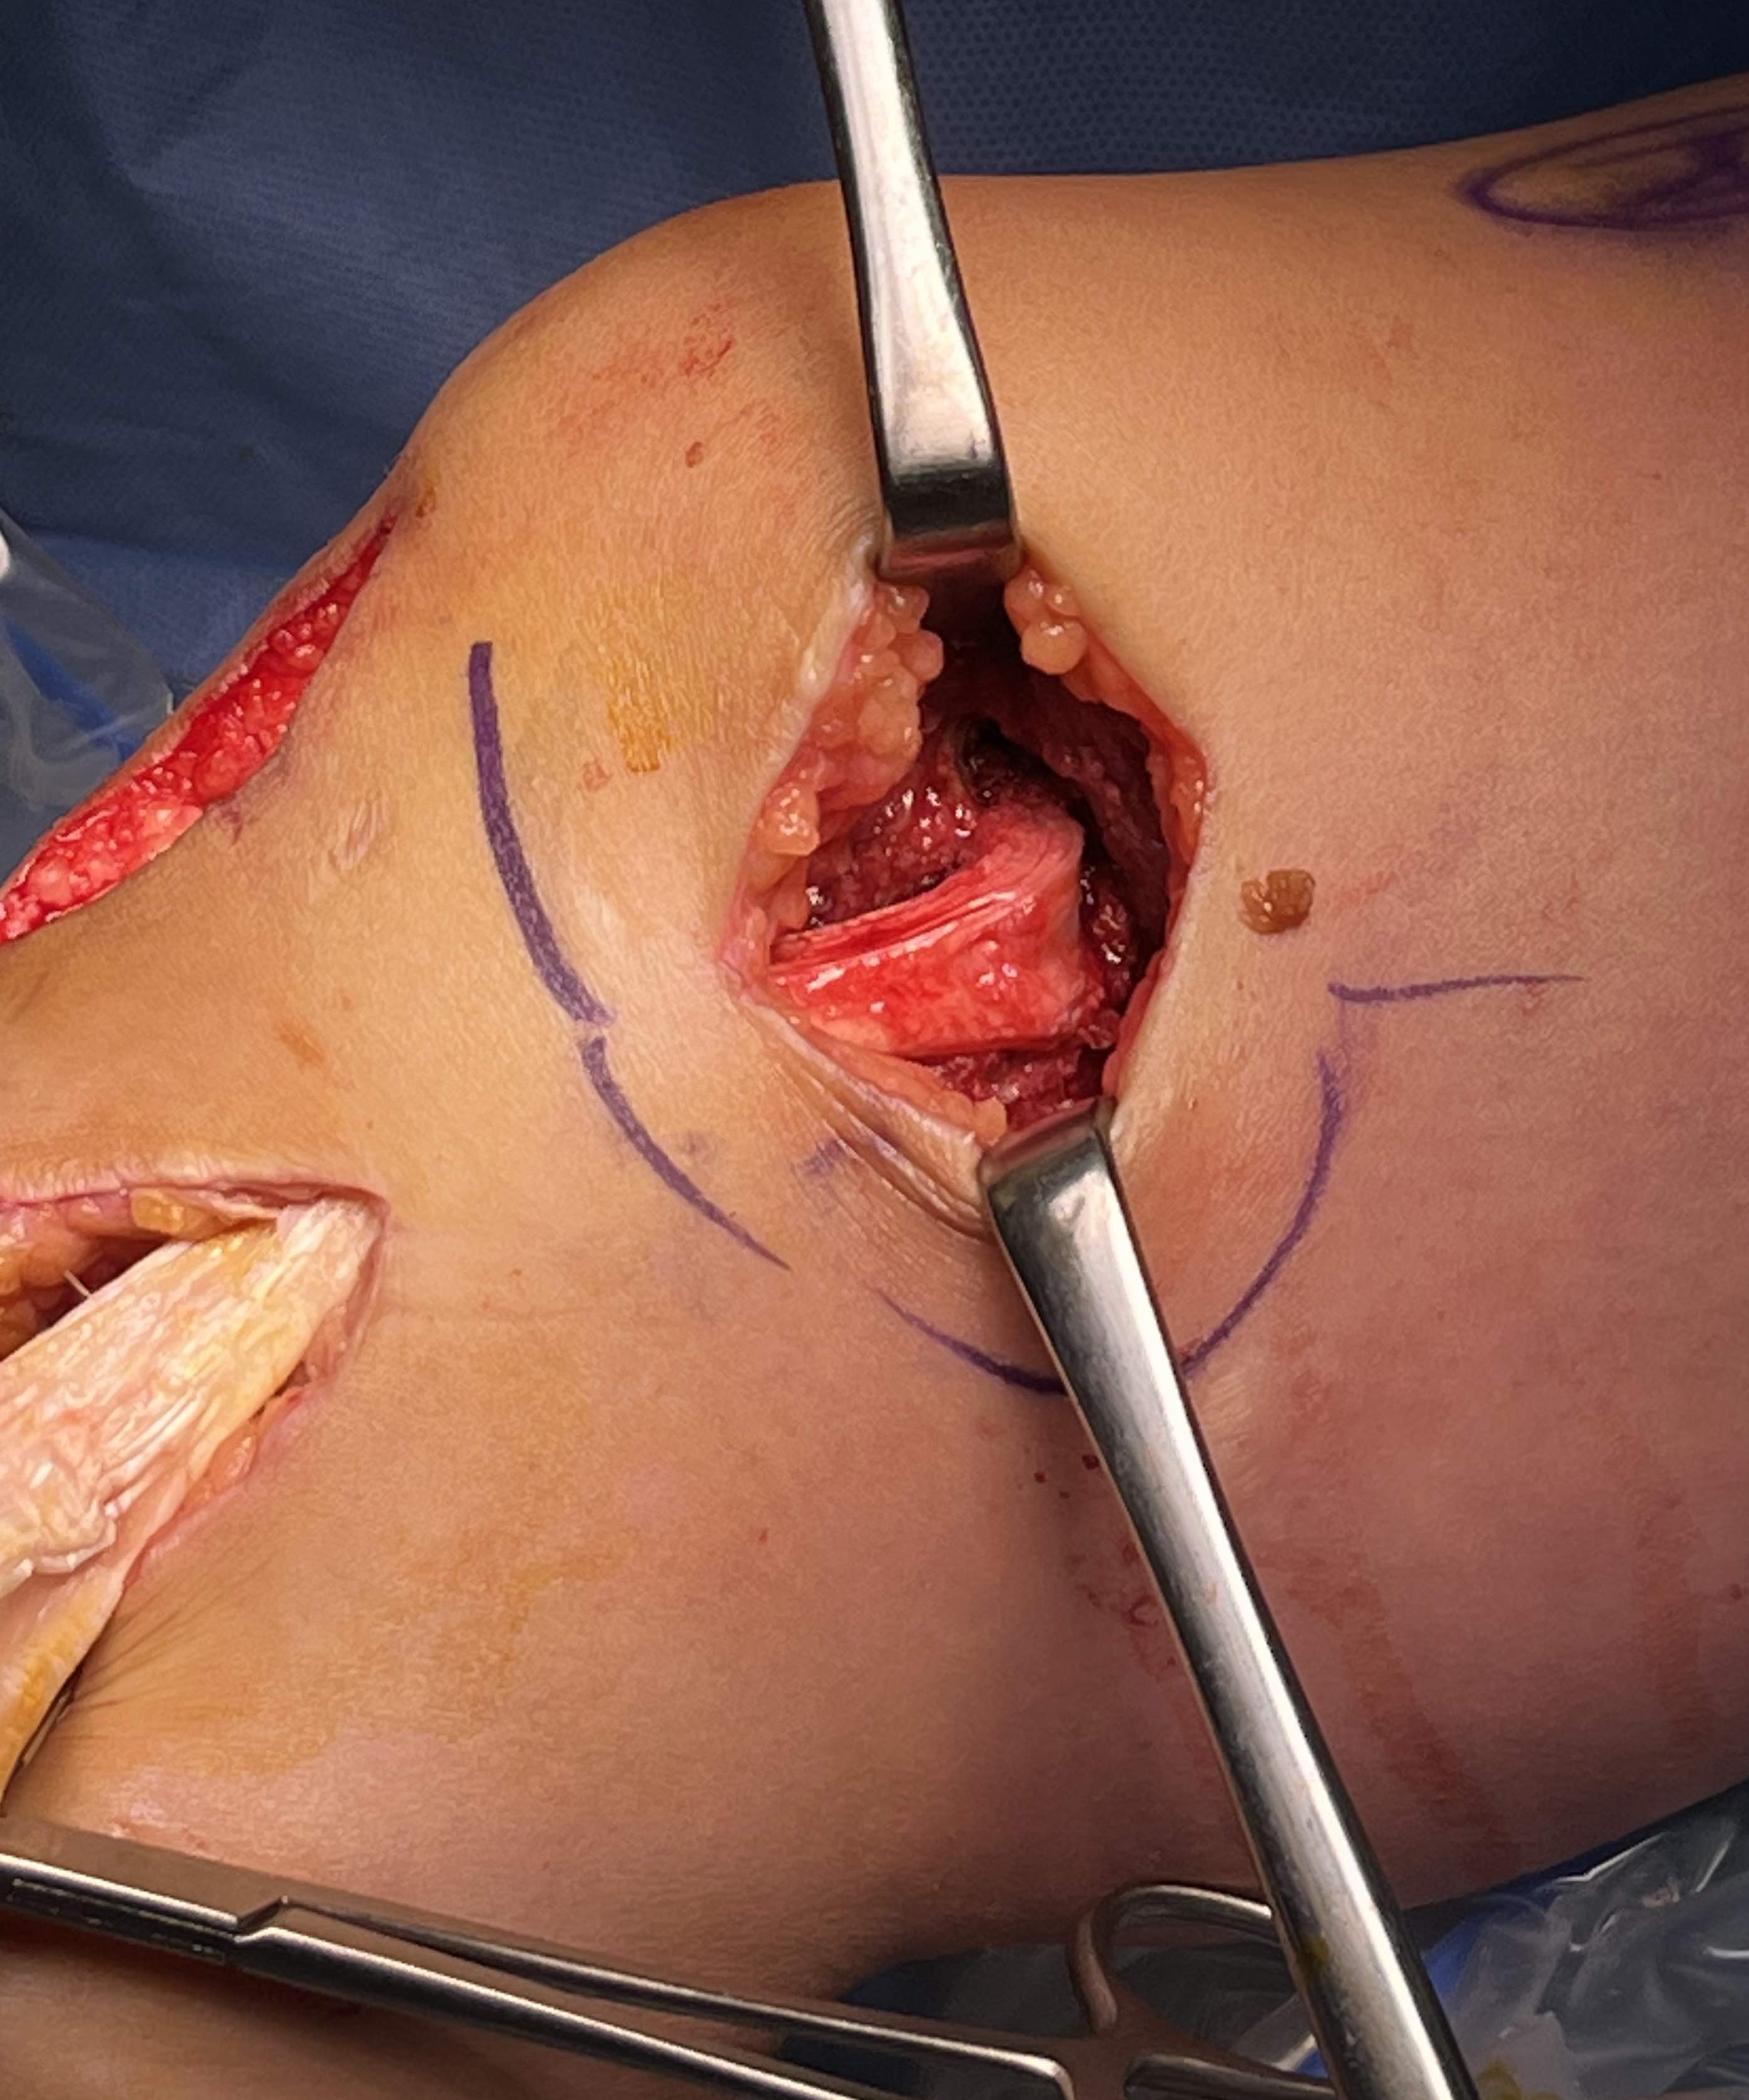

Surgical Approach to Medial Knee

Position

- knee flexed to 90o, over bolster

- tourniquet

- sandbag under hip

Incision

- hockey stick medial incision

- halfway between borders of tibia

- extends proximally to adductor tubercle

- distally to pes anserinus

Superficial dissection

- protect the saphenous nerve and small saphenous vein

- emerges from between sartorius and gracilis

- divide medial patella retinaculum from VMO down

- divide sarfascia over pes anserinus

- reflect pes anserinus inferiorly

Deep dissection

- elevate VMO to identify proximal insertion of superficial MCL

- expose superficial MCL running from medial epicondyle down to tibia under pes

- popliteal oblique ligament and semimembranosus are posterior to MCL

- can expose posterior capsule by carefully reflecting medial gastrocnemius posteriorly